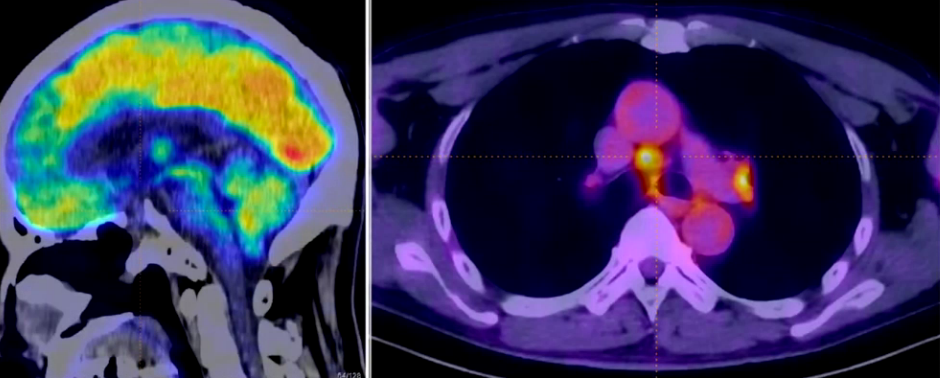

全身PET-CT:提示垂体柄增粗(SUV值4.4),右侧锁骨区、主动脉旁及双肺门淋巴结增大伴代谢增高(SUV值8.1),其余部位无异常代谢信号。

但胸部CT显示两肺弥漫微结节浸润和囊腔样改变,符合朗格汉斯细胞组织细胞增生症影像学表现,且肺门和纵隔多发淋巴结增大。全身PET-CT检查发现垂体柄增粗,SUV值轻微升高,右侧锁骨区、主动脉旁和双肺门淋巴结增大伴低代谢增高。考虑朗格汉斯细胞组织细胞增生症不能除外。